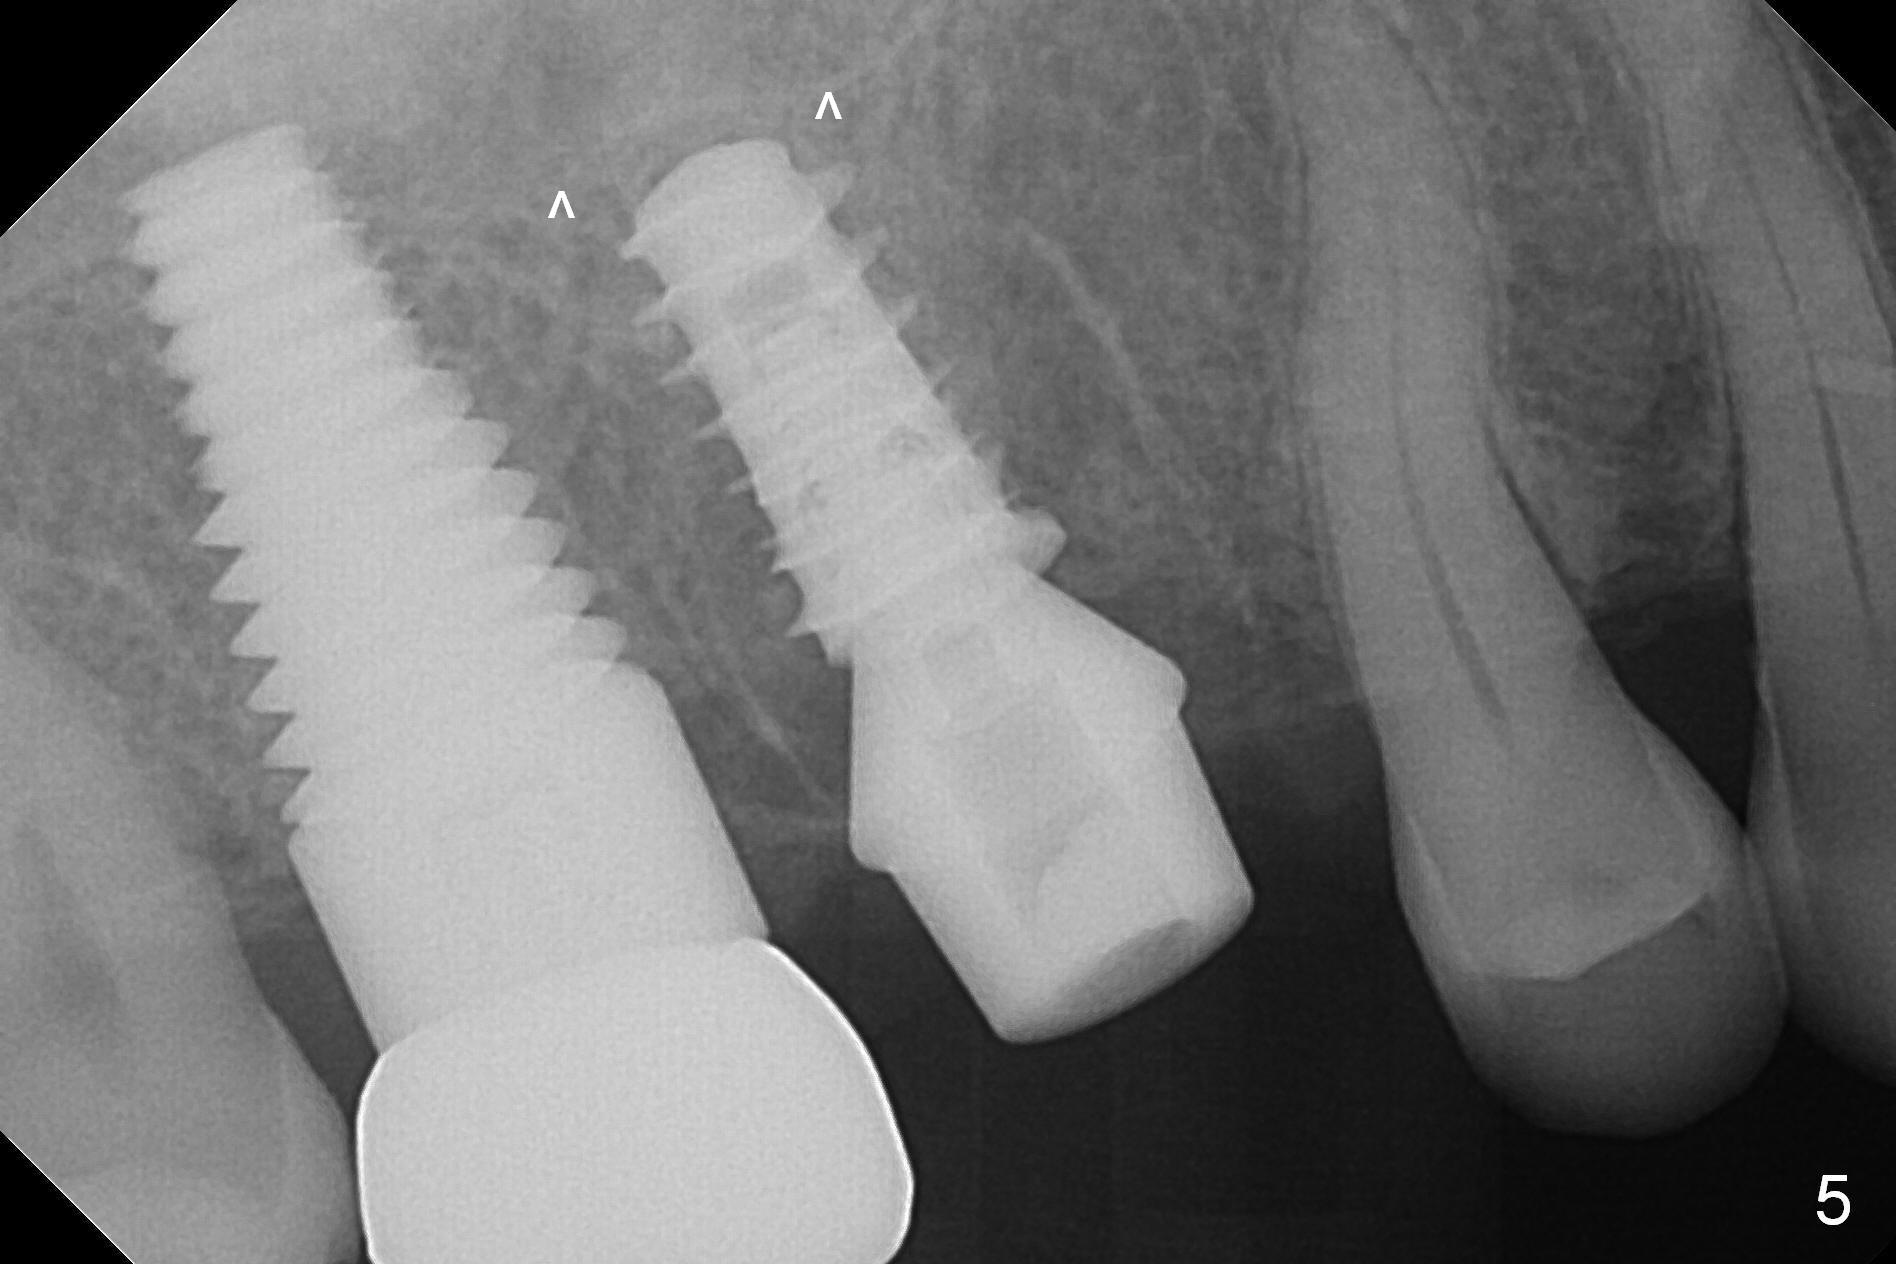

Heavy bruxism is characterized by the crack at #3 (symptomatic, requiring emergency extraction) and loss of the palatal cusp at #5 (Fig.1). Osteotomy is initiated in the septal slope (Fig.2 S) with a 1.6 mm pilot drill for 9 mm (with sudden empty feeling), followed by Marking bur. After 4.3 mm Magic Drill is used for ~ 9 mm, the sinus membrane is found to perforate. A dummy implant (5x9 mm, 2 mm shorter than design) is placed short of the sinus floor (Fig.3 ^). Prior to placement of 5.5x9 mm IBS implant (~ 35 Ncm, Fig.4,5), a piece of Osteogen plug is inserted into the osteotomy for repair of the perforation. The final implant is also shy of the sinus floor (Fig.5 ^). The Osteogen plug is apparently placed underneath the sinus floor so that it should be able to repair hard and soft tissue defects. The remaining sockets are mainly filled with Osteogen plug, while the implant plateau is covered by autogenous bone and Osteogen. When a 6.5x4(3) mm abutment is placed, an immediate provisional is fabricated (Fig.6) with its margin placed subgingival (Fig.6 inset dashed line). This innovative design of the provisional is to prevent collapse of the most coronal gingiva and loss of bone graft, particularly where the bony plate is defective. Although there is mild pain postop, nasal hemorrhage or discharge is absent.

The patient returns with chief complaint of crown is loose with pain 3 months postop (Fig.7). Under local anesthesia, the provisional is removed. The gingiva is erythematous. The implant has mobility. A healing abutment is placed (6x2 mm). One month later, the implant remains unstable. The patient is scheduled to return 3.5 months postop to either retighten the implant with healing screw or replace with a 6x17 mm Tatum implant (Fig.9) after changing trajectory (Fig.8 red arrow).